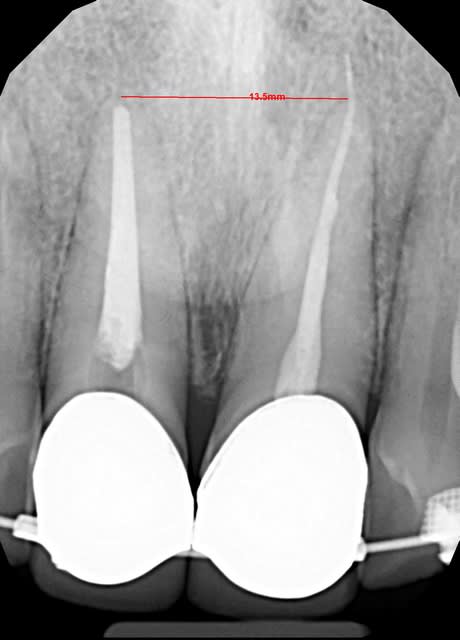

Un patient que je n'avais pas encore vu au cours de la semaine avait RDV ce matin: le praticien m'avait demandé de réaliser le TEI dans la séance de la 22 ayant une LIPOE.

J'ai cathétérisé le canal à la lime 10K, et validé la LT avec une lime 15K avec une radio lime en place.

J'ai amplié le canal au Hero 642 avec une séquence rouge, car canal large mais courbé à l'apex. J'ai irrigué entre chaque instrument au NaOCl, et ai mis de l'EDTA en gel sur chacun de mes instruments mécanisés. Pas d'EDTA liquide disponible au cabinet.

J'ai séché le canal, pas de suintement ni de saignements, j'ai donc décidé d'obturer dans la séance.

J'ai ensuite obturé le canal selon une condensation latérale à froid, avec un ciment inséré au lentulo. Le cabinet n'avait que des cônes calibrés à 25/100e à l'apex. J'ai donc placé celui ci à 0,5mm de ma LT, et j'ai placé deux cônes accessoires en utilisant un figer spreader. J'ai ensuite coupé la Gutta avec un instrument chaud, puis tassé à chaud.

J'ai fait une radio post op montrant un dépassement, que je n'ai développé qu'une fois le patient parti. J'aurais du m'en douter étant donné que l'apex était ouvert du fait de la LIPOE. L'obturation semble dense. Je n'ai pas pu surinstrumenter le canal amicalement car j'avais des stops bien stables, et je vérifiais mes longueurs sur chacun de mes instruments.

Je ne sais pas si le dépassement est juste du ciment, ou si le maitre cône est aussi sorti en tassant.

Img 3657 cwjvqm - Eugenol